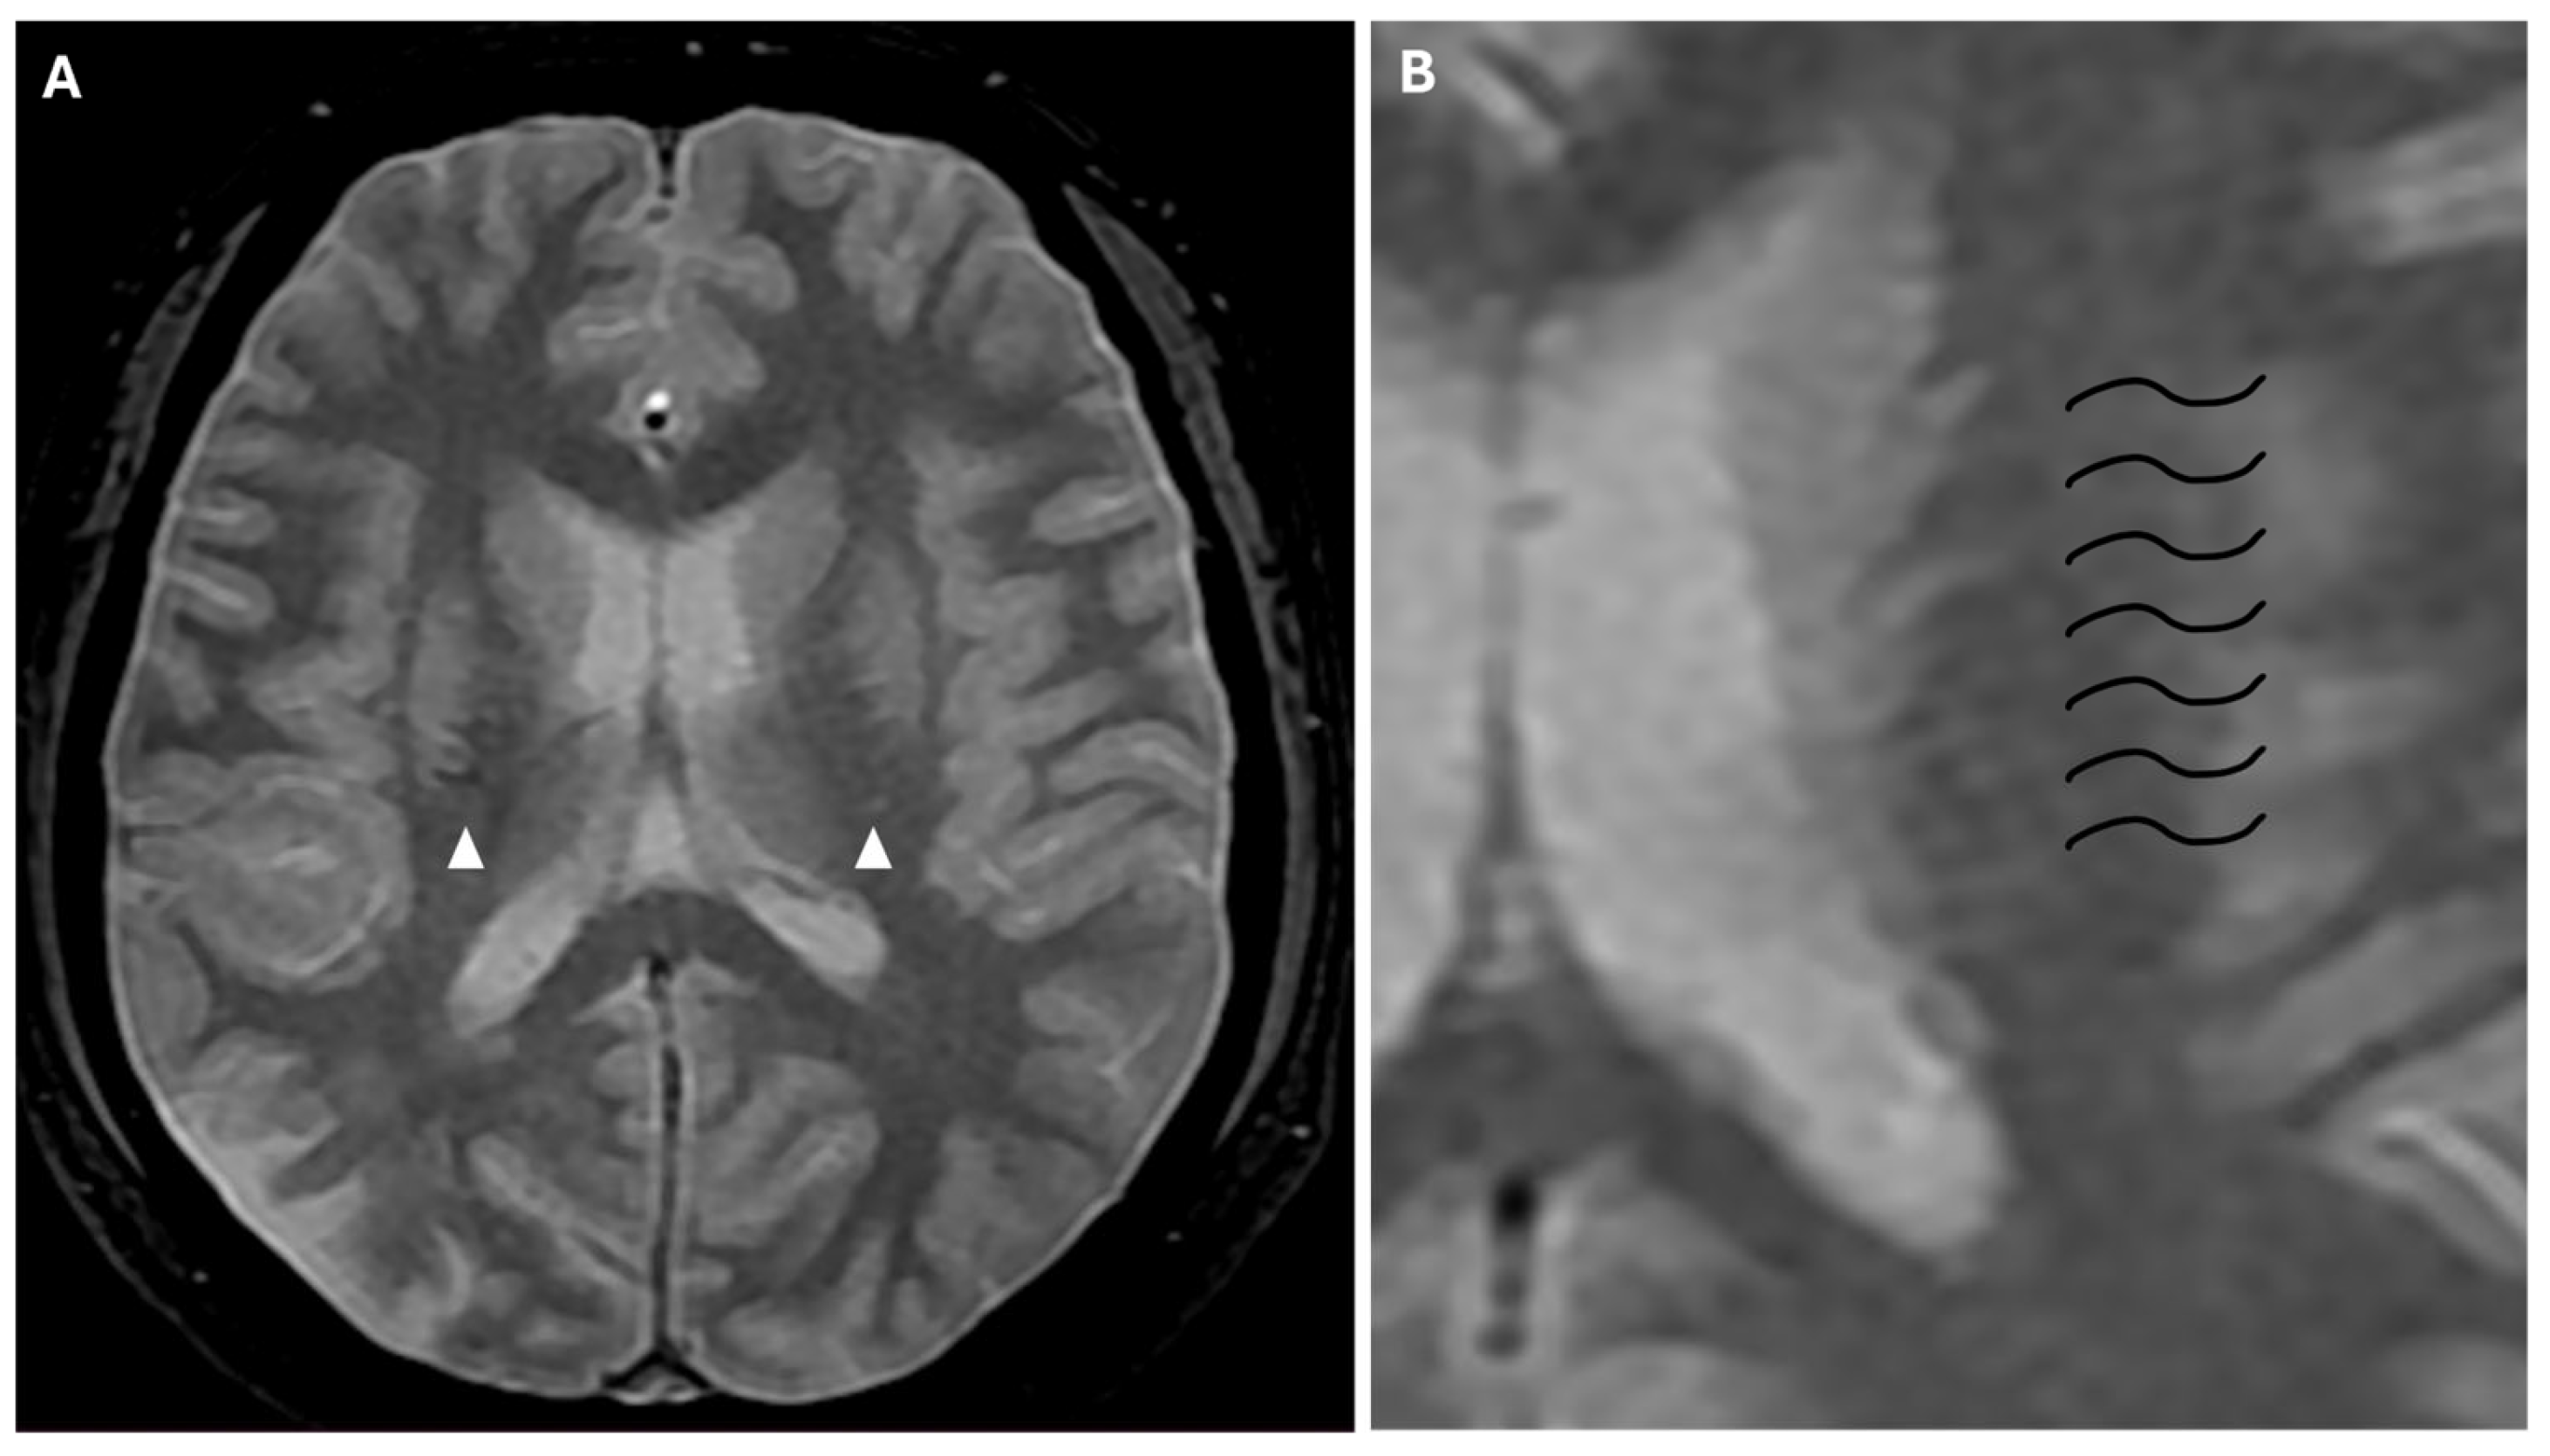

Prominent leptomeningeal collaterals with slow flow, resulting in high signal intensity on FLAIR sequences, were detected in the subarachnoid spaces of the left hemisphere (“ivy sign”) (Figure 4).

The “ivy” sign is an indicator of slow or retrograde flow in engorged pial vessels, via leptomeningeal collaterals, and is characterized by linear hyperintensity on FLAIR sequences in cerebral sulci of the affected brain region, as in the case we report. The ivy sign is also detected on contrast-enhanced T1-weighted sequences, and it may be less pronounced on 3D FLAIR compared to 2D FLAIR sequences, probably because of the differential impact of flow velocity in the 2D versus 3D FLAIR imaging; it has also been hypothesized that the uniform suppression of the cerebrospinal fluid signal inherent to 3D FLAIR may obscure both the abnormal thickening and/or signal intensity of the leptomeninges, as well as pathological signal alterations within the CSF itself [18,19]. In the case we report, this sign was more evident in the brain hemisphere opposite to the ischemic lesion. This apparent paradox could be explained by the rapid onset of arterial occlusion in the right middle cerebral artery that did not allow the development of compensatory collaterals [20]. The ivy sign has been associated with cerebrovascular reactivity and decreased vascular reserve, and, following revascularization surgery, it can improve or worsen temporarily due to hyperperfusion [14]. Moreover, an elevated Suzuki stage (≥3), CBF reduction, and high risk of severe ischemic events, correlate independently with the ivy sign [21].

Figure 8. (A) Axial FFE sequence shows subependymal and medullary veins bilaterally, representing the “prominent vessel sign” (white arrowheads). (B) Magnification of the previous image illustrates deep medullary veins on the left hemisphere (wavy black lines).